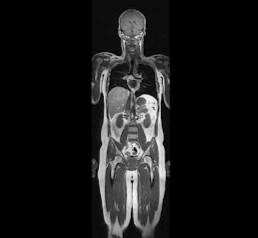

Магнитно-резонансная томография всего тела (Whole body MRI, check-up MRI) является скрининговым, комплексным обследованием всех органов и тканей организма за одну процедуру. 📌В отделении лучевой диагностики №2 данное исследование выполняется на современном МР-томографе Siemens Magnetom Aera 1,5 T и занимает около 50 минут.   🔵Методика обладает рядом важнейших преимуществ, таких как отсутствие лучевой нагрузки, раннее обнаружение асимптоматических очагов воспаления и новообразований, выявление аномалий развития различных органов, высокая разрешающая способность и качество изображений.   Данное исследование не требует какой-либо серьезной подготовки, во время исследования пациент находится в положении лежа на столе томографа, поверх всего тела будут расположены радиочастотные катушки. При необходимости во время исследования внутривенно может быть введено контрастное вещество для уточнения характера выявленных изменений. Противопоказания к проведению МРТ всего тела не отличаются от о

Магнитно-резонансная томография всего тела (Whole body MRI, check-up MRI) является скрининговым, комплексным обследованием всех органов и тканей организма за одну процедуру.

📌В отделении лучевой диагностики №2 данное исследование выполняется на современном МР-томографе Siemens Magnetom Aera 1,5 T и занимает около 50 минут.

🔵Методика обладает рядом важнейших преимуществ, таких как отсутствие лучевой нагрузки, раннее обнаружение асимптоматических очагов воспаления и новообразований, выявление аномалий развития различных органов, высокая разрешающая способность и качество изображений.

Данное исследование не требует какой-либо серьезной подготовки, во время исследования пациент находится в положении лежа на столе томографа, поверх всего тела будут расположены радиочастотные катушки. При необходимости во время исследования внутривенно может быть введено контрастное вещество для уточнения характера выявленных изменений.